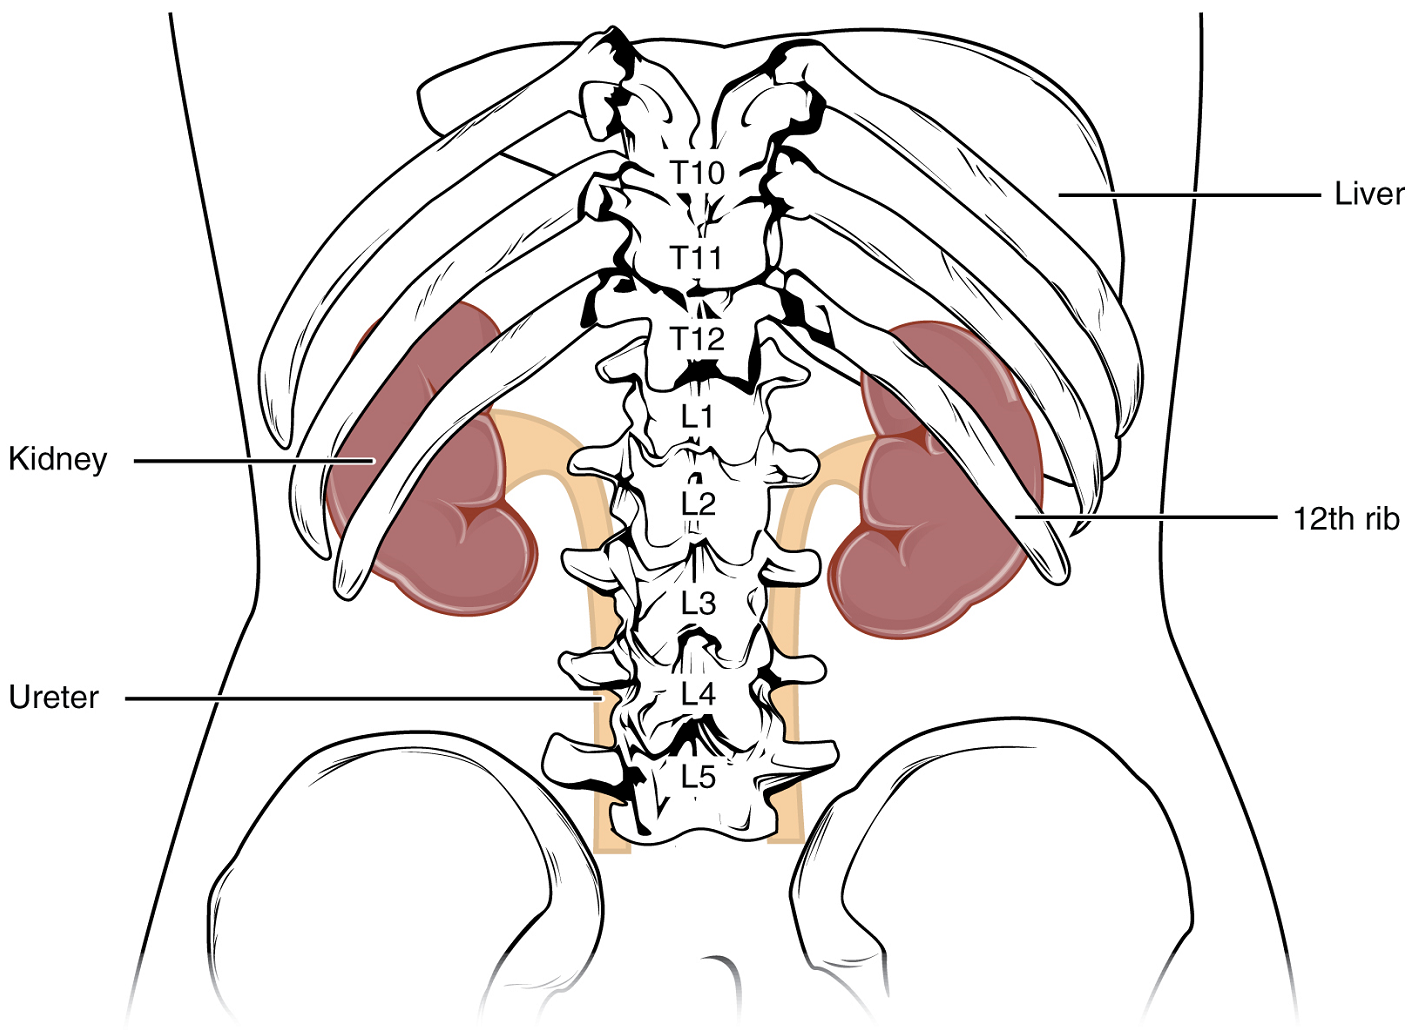

The kidneys lie on either side of the spine in the retroperitoneal space between the parietal peritoneum and the posterior abdominal wall, well protected by muscle, fat, and ribs. They are roughly the size of your fist. The kidneys are well vascularized, receiving about 25 percent of the cardiac output at rest.

External Anatomy: The left kidney is located at about the T12 to L3 vertebrae, whereas the right is lower due to slight displacement by the liver. Upper portions of the kidneys are somewhat protected by the eleventh and twelfth ribs (Figure 1). Each kidney weighs about 125–175 g in males and 115–155 g in females. They are about 11–14 cm in length, 6 cm wide, and 4 cm thick, and are directly covered by a fibrous capsule composed of dense, irregular connective tissue that helps to hold their shape and protect them.

This capsule is covered by a shock-absorbing layer of adipose tissue called the renal fat pad. On the superior aspect of each kidney is the adrenal gland.